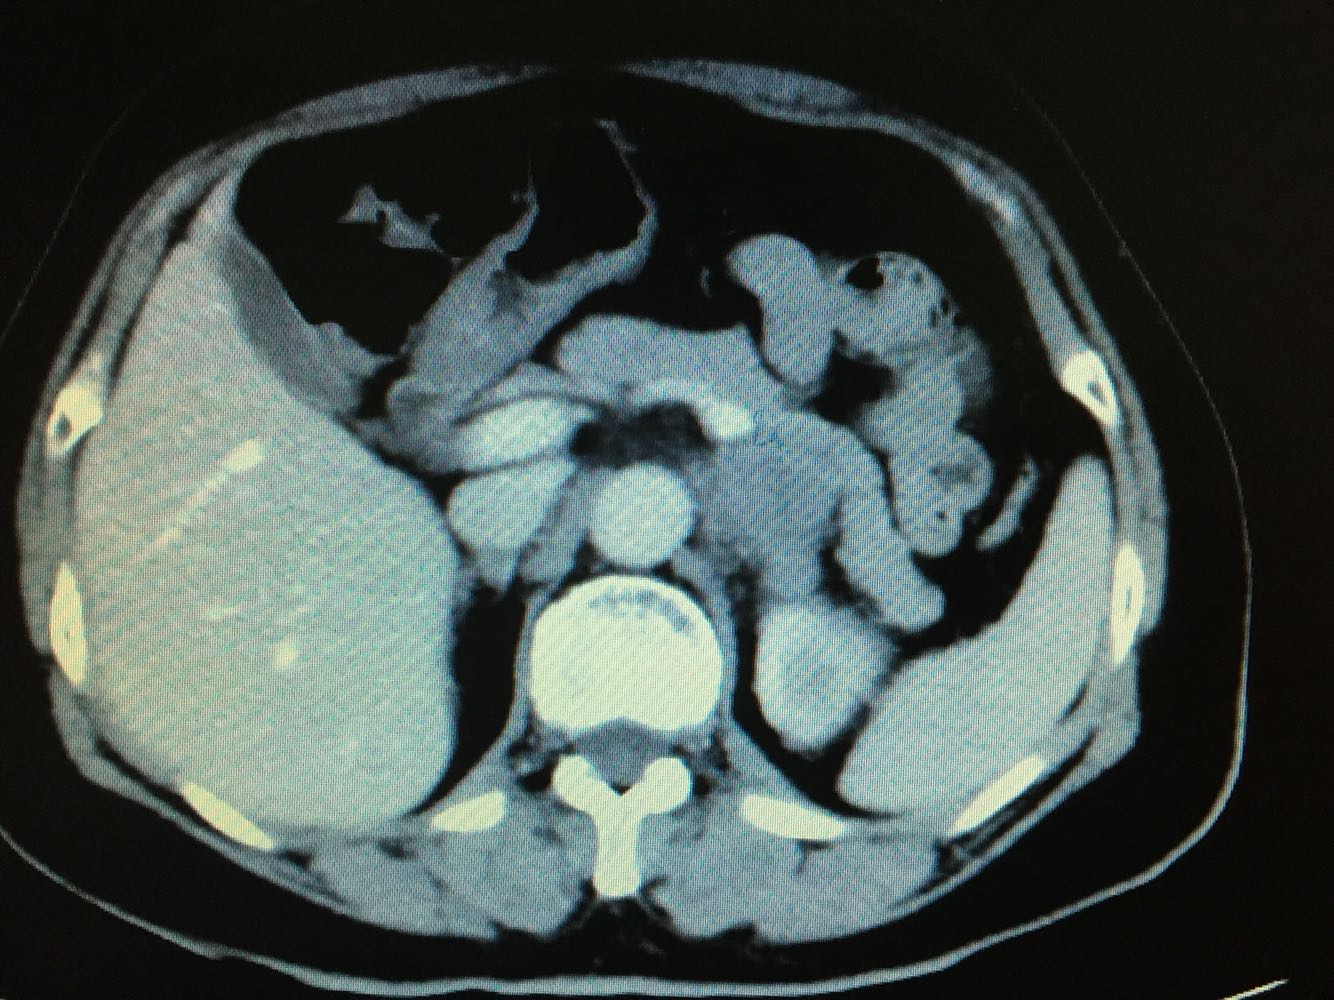

CT提示,左侧肾门处雪人样占位,包裹左肾静脉,左肾积水,与胰腺及左肾关系密切,血常规,肝肾功未见明显异常,GFR左侧27,右侧58。

诊断,左侧腹膜后占位:淋巴瘤?或者淋巴样增生?,侵犯周围器官组织?